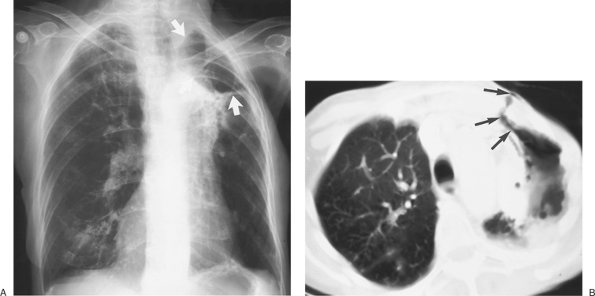

FIGURE 9-16. Malignant pleural effusion. A: PA chest radiograph of an 83-year-old woman with metastatic right breast cancer shows a large right pleural effusion and interstitial lung disease. B: CT after drainage of right pleural fluid shows nodular thickening of the vascular structures and pulmonary septae on the right, characteristic of lymphangitic carcinomatosis.